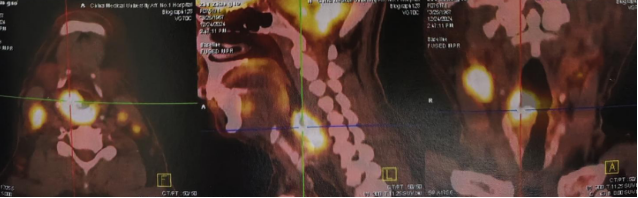

The patient experienced difficulty swallowing without apparent cause on July 1, 2024, with no symptoms of hoarseness or breathing difficulties. The symptoms worsened compared to before by December 2024. On December 24, 2024, the patient sought medical attention at the First Affiliated Hospital of China Medical University. An otolaryngology electronic laryngoscopy examination revealed an irregular new growth located on the outer wall of the right piriform fossa, retropharynx, esophageal inlet, bilateral tonsillar fossae, bilateral piriform sinuses, posterior wall of the hypopharynx, right lateral wall of the hypopharynx, and right tonsillar pillar. PET-CT showed irregular soft tissue shadows with increased metabolism (SUV of 31.7) in the right piriform fossa area and posterior region, right lateral and posterior walls of the hypopharynx, and upper end of the esophagus, suggesting a high likelihood of malignant lesions. Additionally, multiple enlarged lymph nodes were observed in the bilateral neck and supraclavicular regions, with the largest diameter measuring approximately 19mm and increased metabolism (SUV of 22.2), indicating likely metastases from malignant lesions.